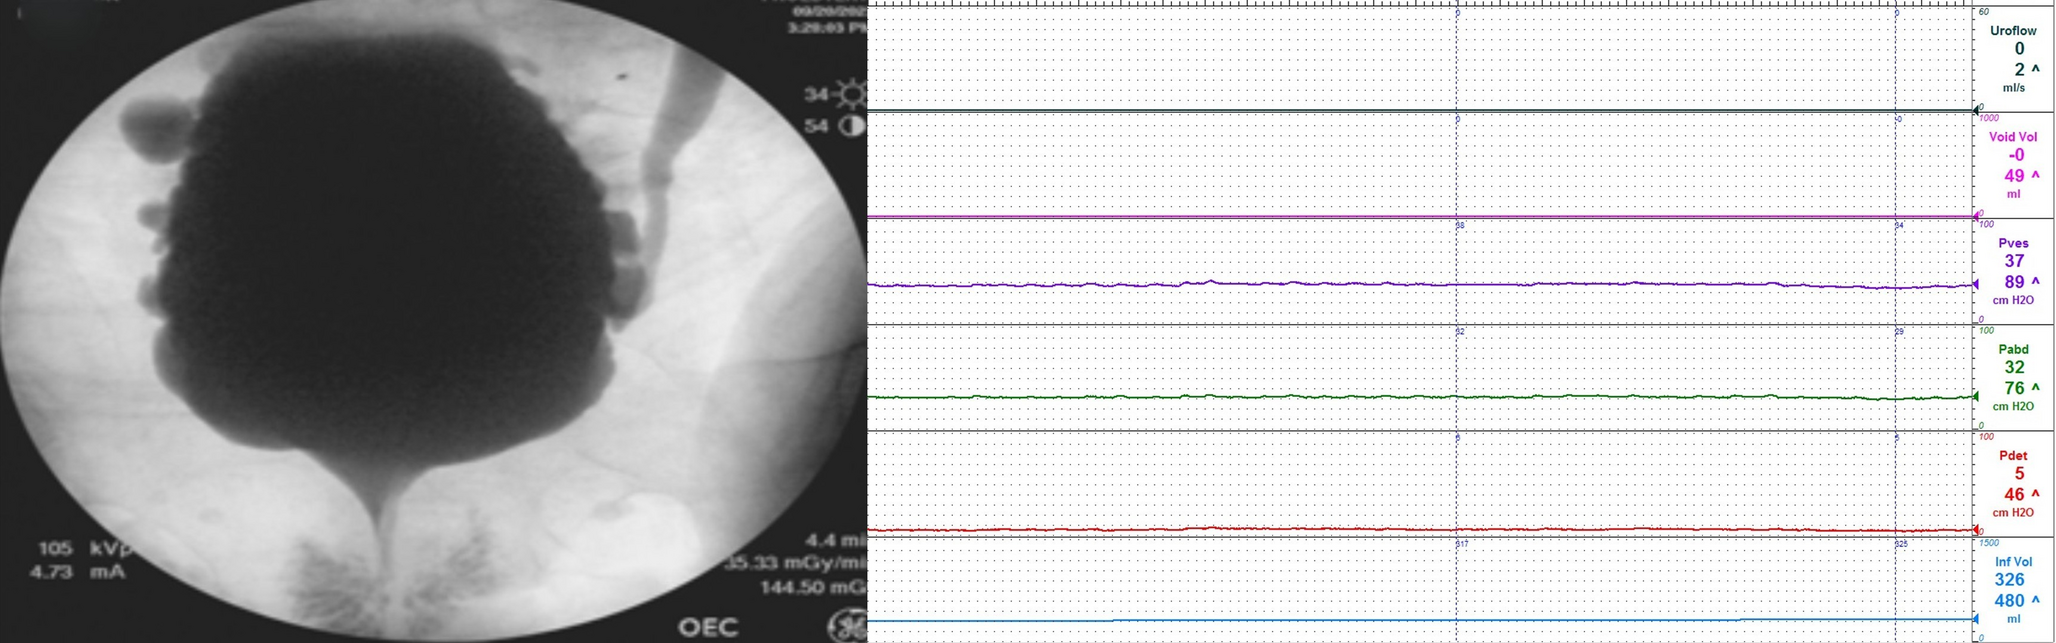

Management of Persistent UI after AUS ImplantationManaging persistent UI following AUS implantation in patients who have undergone RT requires a multifaceted approach. Radiation-induced changes, such as fibrosis and reduced vascularity in the urethra, bladder wall structure, and detrusor function [5], often necessitate tailored interventions. One key strategy is the thorough pre-operative assessment of urethral and bladder function. This includes urodynamic studies to evaluate bladder compliance, capacity, and detrusor overactivity.

In such cases of persistent UI after AUS implantation, further investigations need to be performed to evaluate the cause of the incontinence. This involves a urethroscopic examination and a urodynamics study. If there is detrusor overactivity present, pharmacologic management, such as anticholinergics or beta-3 agonists should be started as first line therapy.